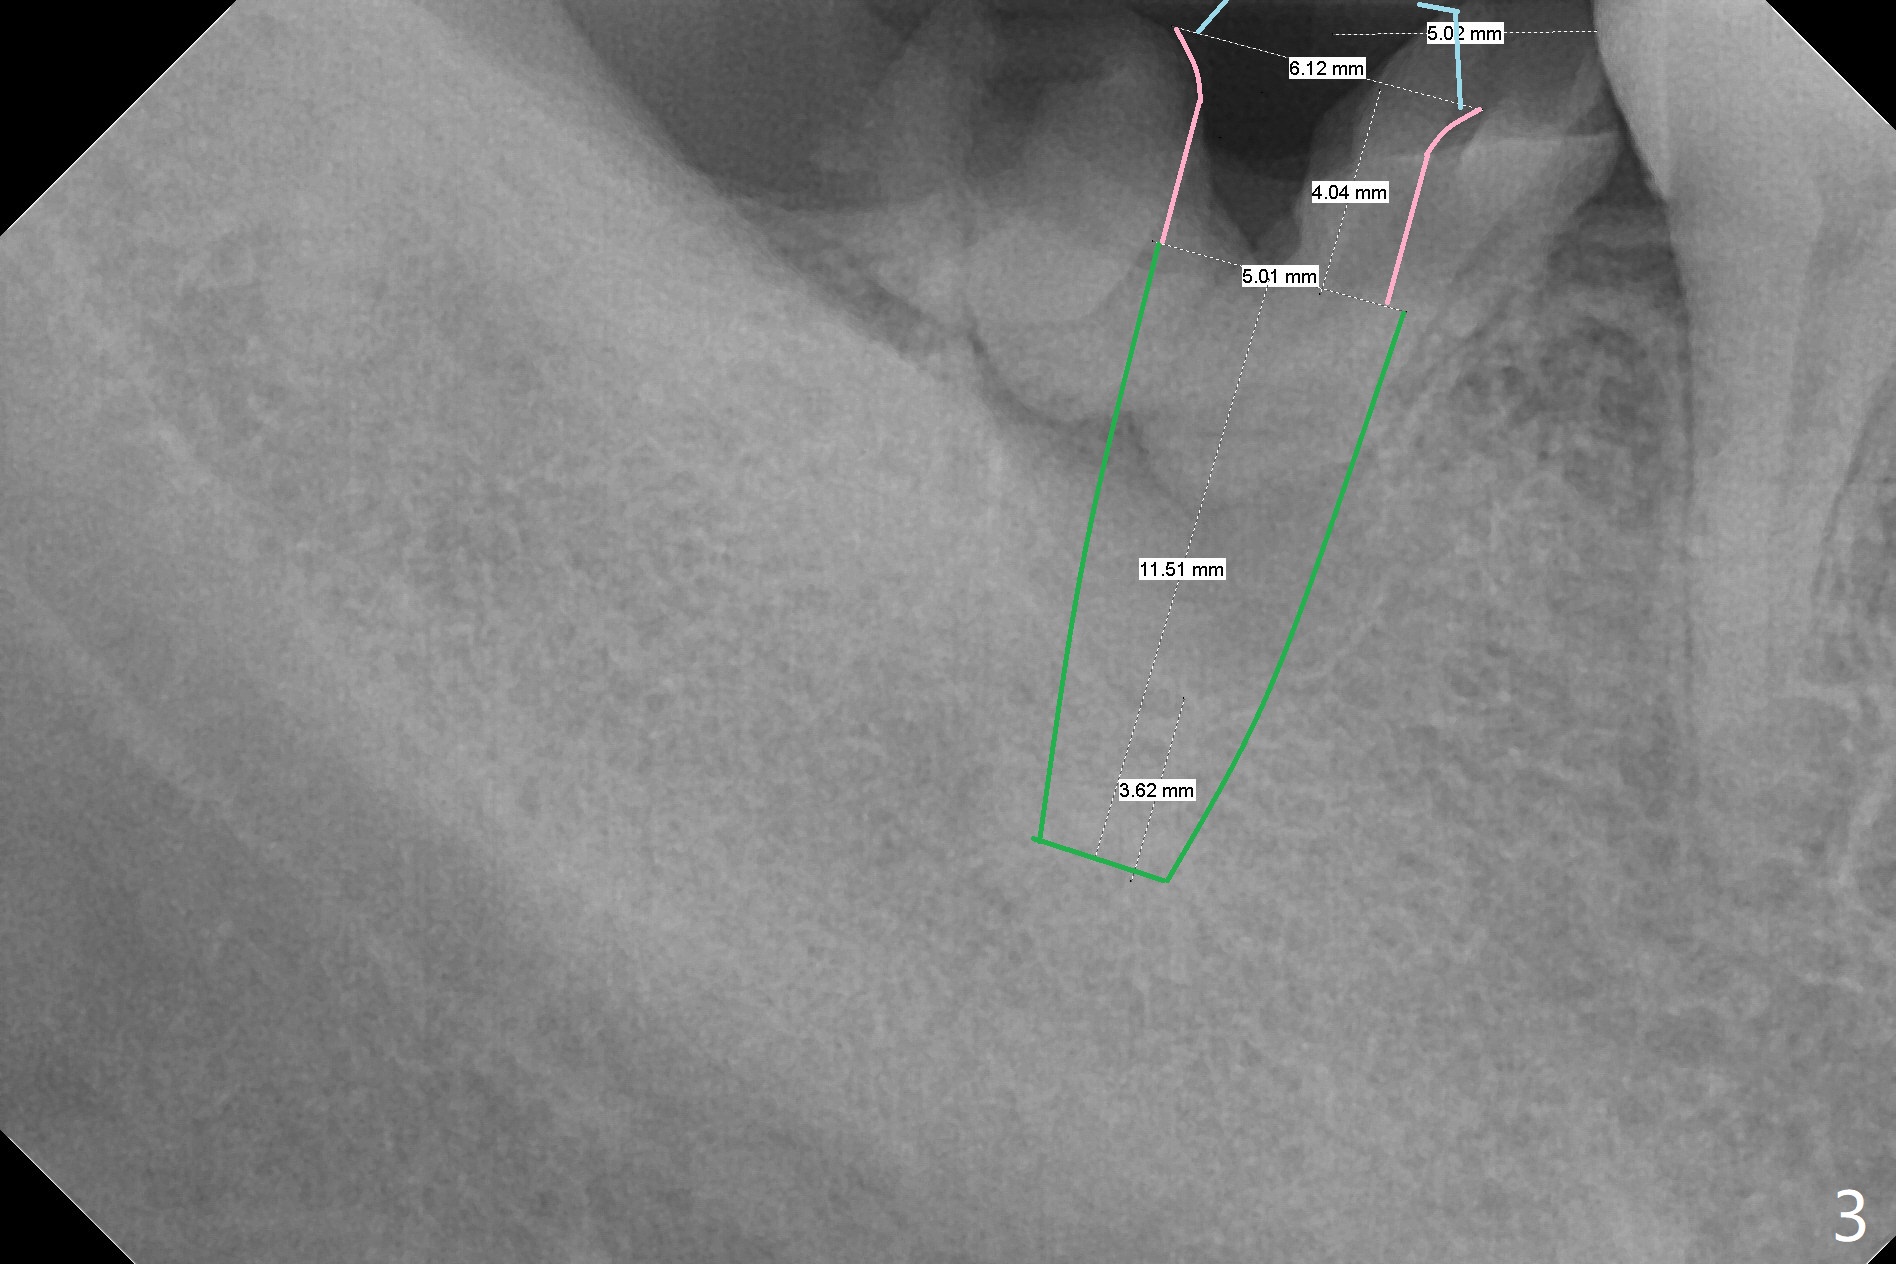

A 39-year-old man finishes orthodontic treatment without intrusion of the upper 2nd molar (Fig.1). He is reluctant for mini-implant placement for intrusion. After extraction of the tooth #31 with periapical radiolucency (Fig.2 *), a 5x11(4) mm Magicore will be placed with guide (Fig.3). Following osteointegration (Fig.4), a burn out core is going to be placed (Fig.5 brown, inside metal, outside plastic). With proper height adjustment, a provisional is fabricated around the core with acrylic (Fig.6 white). If the provisional keeps breaking down under occlusion, the case will be sent to lab for a screw retained crown with unfinished rough occlusal surface so that a thin layer restoration material able to be laid chair-side (acrylic or suction down material). Over time, the opposing tooth will be intruded (Fig.7 arrow).